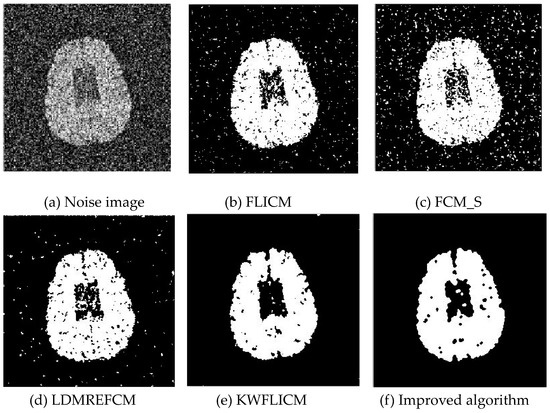

Gaussian noise was added to two remote sensing images with a mean value of 0 and mean variances of 57 and 80. Gaussian noise was added to images containing four artificial categories, brain CT (Computed Tomography) images, and camera images with a mean value of 0 and mean variances of 140 and 161. The number of clusters was set to 3, 4, 2, and 2. The results were compared using the results from the FLICM, FCM_S, LDMREFCM, and KWFLICM algorithms and the improved algorithm. The original image is shown in Figure 1, and the experimental results are shown in Figure 2, Figure 3, Figure 4 and Figure 5 (b–f). The error rate and PSNR of the segmentation results are shown in Table 1 and Table 2, and the iteration time and the number of iterations are shown in Table 3 [40,41].

3.1.2. Test Result

Comparing the segmentation results of the five algorithms in Figure 2, Figure 3, Figure 4 and Figure 5 for four images with different degrees of Gaussian noise interference, we can see that the segmentation results of the FCM_S, FLICM, and LDMREFCM algorithms still contained many noise points; the KWFLICM algorithm contained fewer noise points; while the improved algorithm has the fewest noise points. Table 1 shows that the improved algorithm had the highest signal-to-noise ratio compared with the other four algorithms, which shows that the improved algorithm had the strongest anti-Gaussian noise ability. Table 2 shows that the segmentation result of the improved algorithm was the smallest of all the algorithms, which shows that the segmentation result of the improved algorithm was closer to the ideal segmentation result and had a better segmentation performance. Comparing the PSNR and iteration time of each algorithm in Table 3, the average PSNR of the improved algorithm was 0.7 dB higher than that of the KWFLICM algorithm, and the average iteration time of the improved algorithm was 500 s less than that of the KWFLICM algorithm [42,43]. The iteration times of the FCM_S and FLICM algorithms were the lowest, but the difference between the improved algorithm results and the PSNR was 2–5 dB. The anti-noise ability of the FLCM and FCM_S method was poor. Combining the PSNR test results and the iteration time, the improved algorithm had a better anti-Gaussian noise segmentation performance.

Figure 4. Gaussian noise interfering with the brain slice image (a) and the segmentation results (bf).